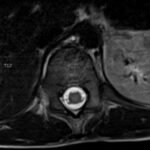

There is a growing body of literature and scientific discovery on pediatric autoimmune encephalitides. This is a heterogenous group of neuroinflammatory conditions leading to often perplexing acute and progressive neurologic and/or neuropsychiatric symptoms. This report demonstrates the evaluation and management of an adolescent with myelin-oligodendrocyte glycoprotein (MOG) antibody-associated fulminant acute disseminated encephalomyelitis (ADEM) in the context of current literature. The featured magnetic resonance imaging uniquely highlights progressive central nervous system lesions detected over the course of the first week of disease.